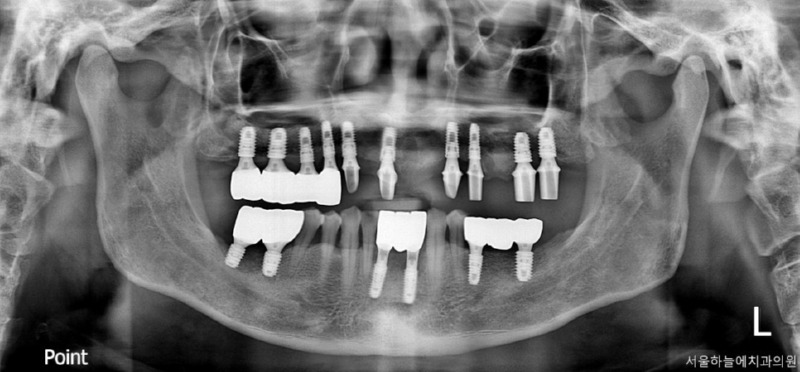

이번에 소개해드릴 환자분은

당뇨와 고혈압, 두 가지 전신질환을

모두 가지고 계셨던 분으로

치아 결손이 광범위해

전악 임플란트가 필요한 상황이었습니다.

· 상악은 잇몸뼈가 매우 얇고 치아가 거의 남아 있지 않은 상태

· 하악은 부분 결손과 앞니의 심한 동요

· 식사가 어려울 정도로 기능 저하가 심한 상태

치료 계획 및 수술 과정

이 환자분은 다음과 같은 계획으로

치료를 진행했습니다.

· 수면마취(의식하 진정요법) 하에 진행

· 상악 양측 상악동 거상술 + 임플란트 10개 식립

· 하악 발치 후 결손 부위 포함 임플란트 6개 식립